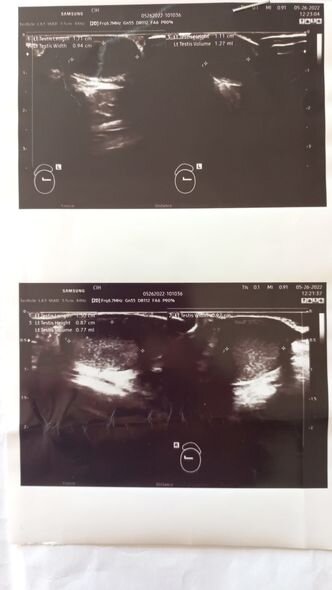

O bildirib ki, övladı anadangəlmə kriptorxizm (enməmiş testis anlayışı ilə sinonim olub, xayanın xayalıqda olmadığı bütün hallar) xəstəliyindən əziyyət çəkir.

"İslamın 11 yaşı var, o illərdir kriptorxizm xəstəliyindən əziyyət çəkir. O, bir neçə il öncə bu xəstəliyə görə əməliyyat keçirsə də, əməliyyat uğursuz nəticələnib. 3 ay öncə övladımın şiddətli ağrılarına görə onu həkimə apardıq. Həkimlər onun xayalarının yerində olmadığını dedilər. Hazırda o, yenidən əməliyyat olunmalıdır. Bunun üçün isə 3 200 manata ehtiyacımız var. İnanın, bu əməliyyatı qarşılamağa imkanımız yoxdur. Özümüz kirayədə yaşayırıq, yoldaşım isə fəhlə işləyir. Yardımsevər şəxslərdən bizə dəstək olmalarını xahiş edirəm".